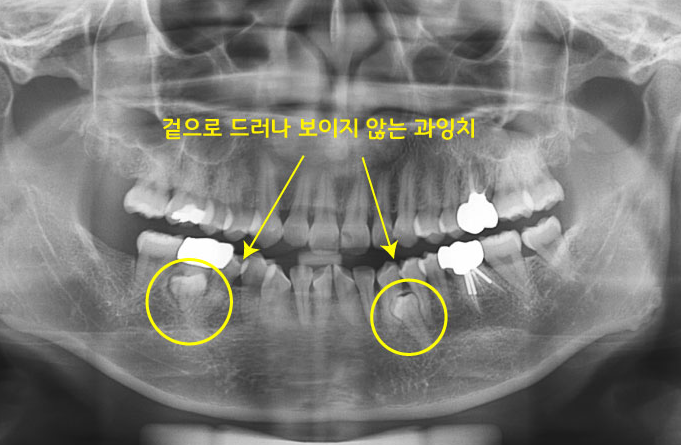

사진을 보면 아래에 보이지 않는 과잉치가 숨어있는 것을 볼 수 있어요. 모든 과잉치가 해당되는 것아는 니며 과잉치의 위치와 크기, 주변 치아와의 관계를 충분히 살펴본 후에 치과 전문의의 소견에 따라 치아교정을 시행해볼 수 있는데요. 잇몸 속이나 턱뼈 속에 숨어있어 눈에 띄지 않는 과잉치들이 많으니 이런 경우에는 엑스레이나 CT 촬영을 통해 확인해볼 수 있어요.